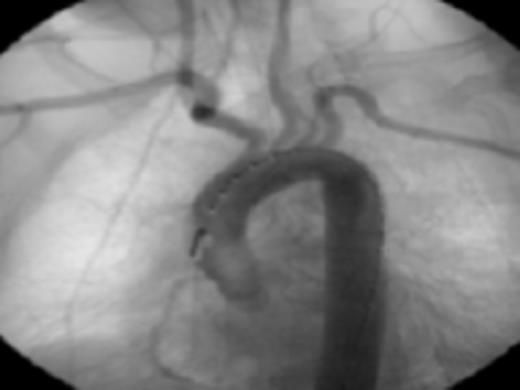

Diagnostic aortic angiography demonstrating darkening distal to the left subclavian possibly representing plaque. Image prior to stent deployment

Her past medical history of considerable GI bleeds and her significant fall risk made her a poor candidate for continued anti-coagulation therapy. The appropriateness of the lesion involved and her risk for further embolic events guided selection of endovascular technique for treatment. Exclusion was performed by a 26mm × 10cm thoracic aortic stent graft with balloon angioplasty. Post-procedure angiography confirmed position of the graft distal to the origins of the great vessels and did not demonstrate any leaks. Subsequently, she progressed well and was discharged in stable condition on warfarin and clopidogrel.

Fig 4: Post endovascular stenting angiography showing appropriate seal without leaks or extravasation of contrast